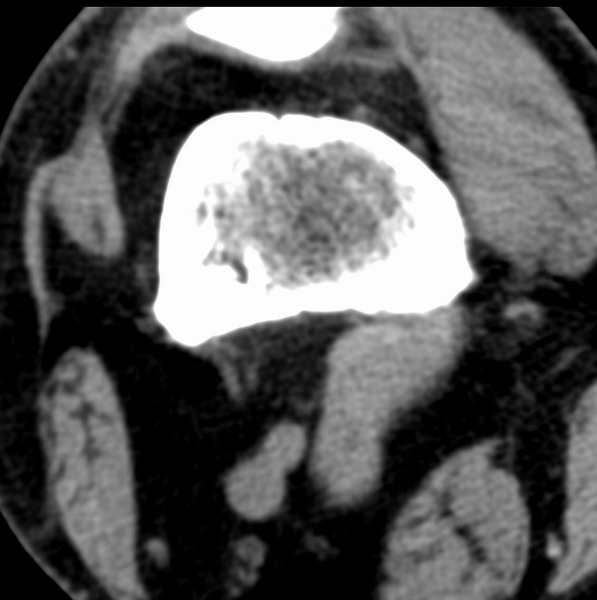

标题: CT21959:骨肿瘤请会诊。

右侧膝关节疼痛一月

男、48

股骨下段、胫骨上段。

1、股骨干骺端病变考虑干骺端纤维性皮质缺损愈后(非骨化性纤维瘤)改变,胫骨近端内生骨瘤(或干骺端纤维性皮质缺损愈后改变);

2、骨关节炎,骨质增生,股骨外侧髁退变性囊肿(关节面软骨下囊肿);

股骨干骺端病变考虑干骺端纤维性皮质缺损愈后(非骨化性纤维瘤)改变,胫骨近端内生骨瘤(或干骺端纤维性皮质缺损愈后改变);

多发内生软骨瘤!

股骨干骺端病变考虑非骨化性纤维瘤。

1、股骨干骺端病变考虑干骺端纤维性皮质缺损愈后(非骨化性纤维瘤)改变,胫骨近端内生骨瘤;